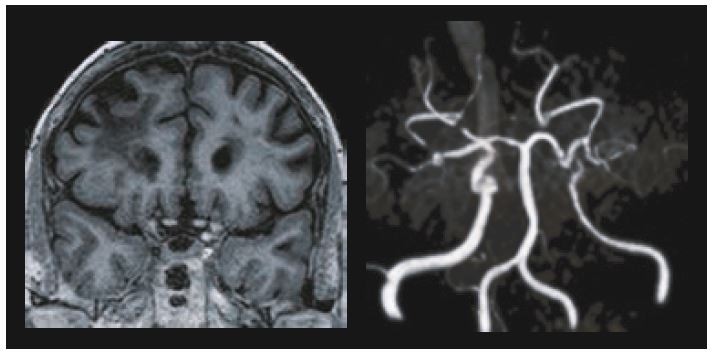

Прогресуюче звуження або повна обструкція мозкових артерій характеризує хворобу Мойя Мойя. Ці артерії відповідають за постачання мозку киснем і поживними речовинами. Для компенсації нестачі кисню розвивається багато вторинних капілярів. Це захворювання більш поширене в Японії, і його назва походить від зовнішнього вигляду цих капілярів, які виглядають як «клуб диму» («Мойя Мойя» японською). Також тут ASL може мати значну додаткову цінність у протоколі. На рисунку 6 показано пацієнта з хворобою Мойя Мойя, який переніс енцефало-дуро-артеріо-міо-синангіоз.

Рис. 6. Корональна MPR MPRAGE показує ішемічні ускладнення правої лобної частини.

Рис. 7. Після операції ASL-послідовність показує нормальну перфузію мозку. Осьовий MPR Flair показує деякі інсультні порожнини з гліозом.